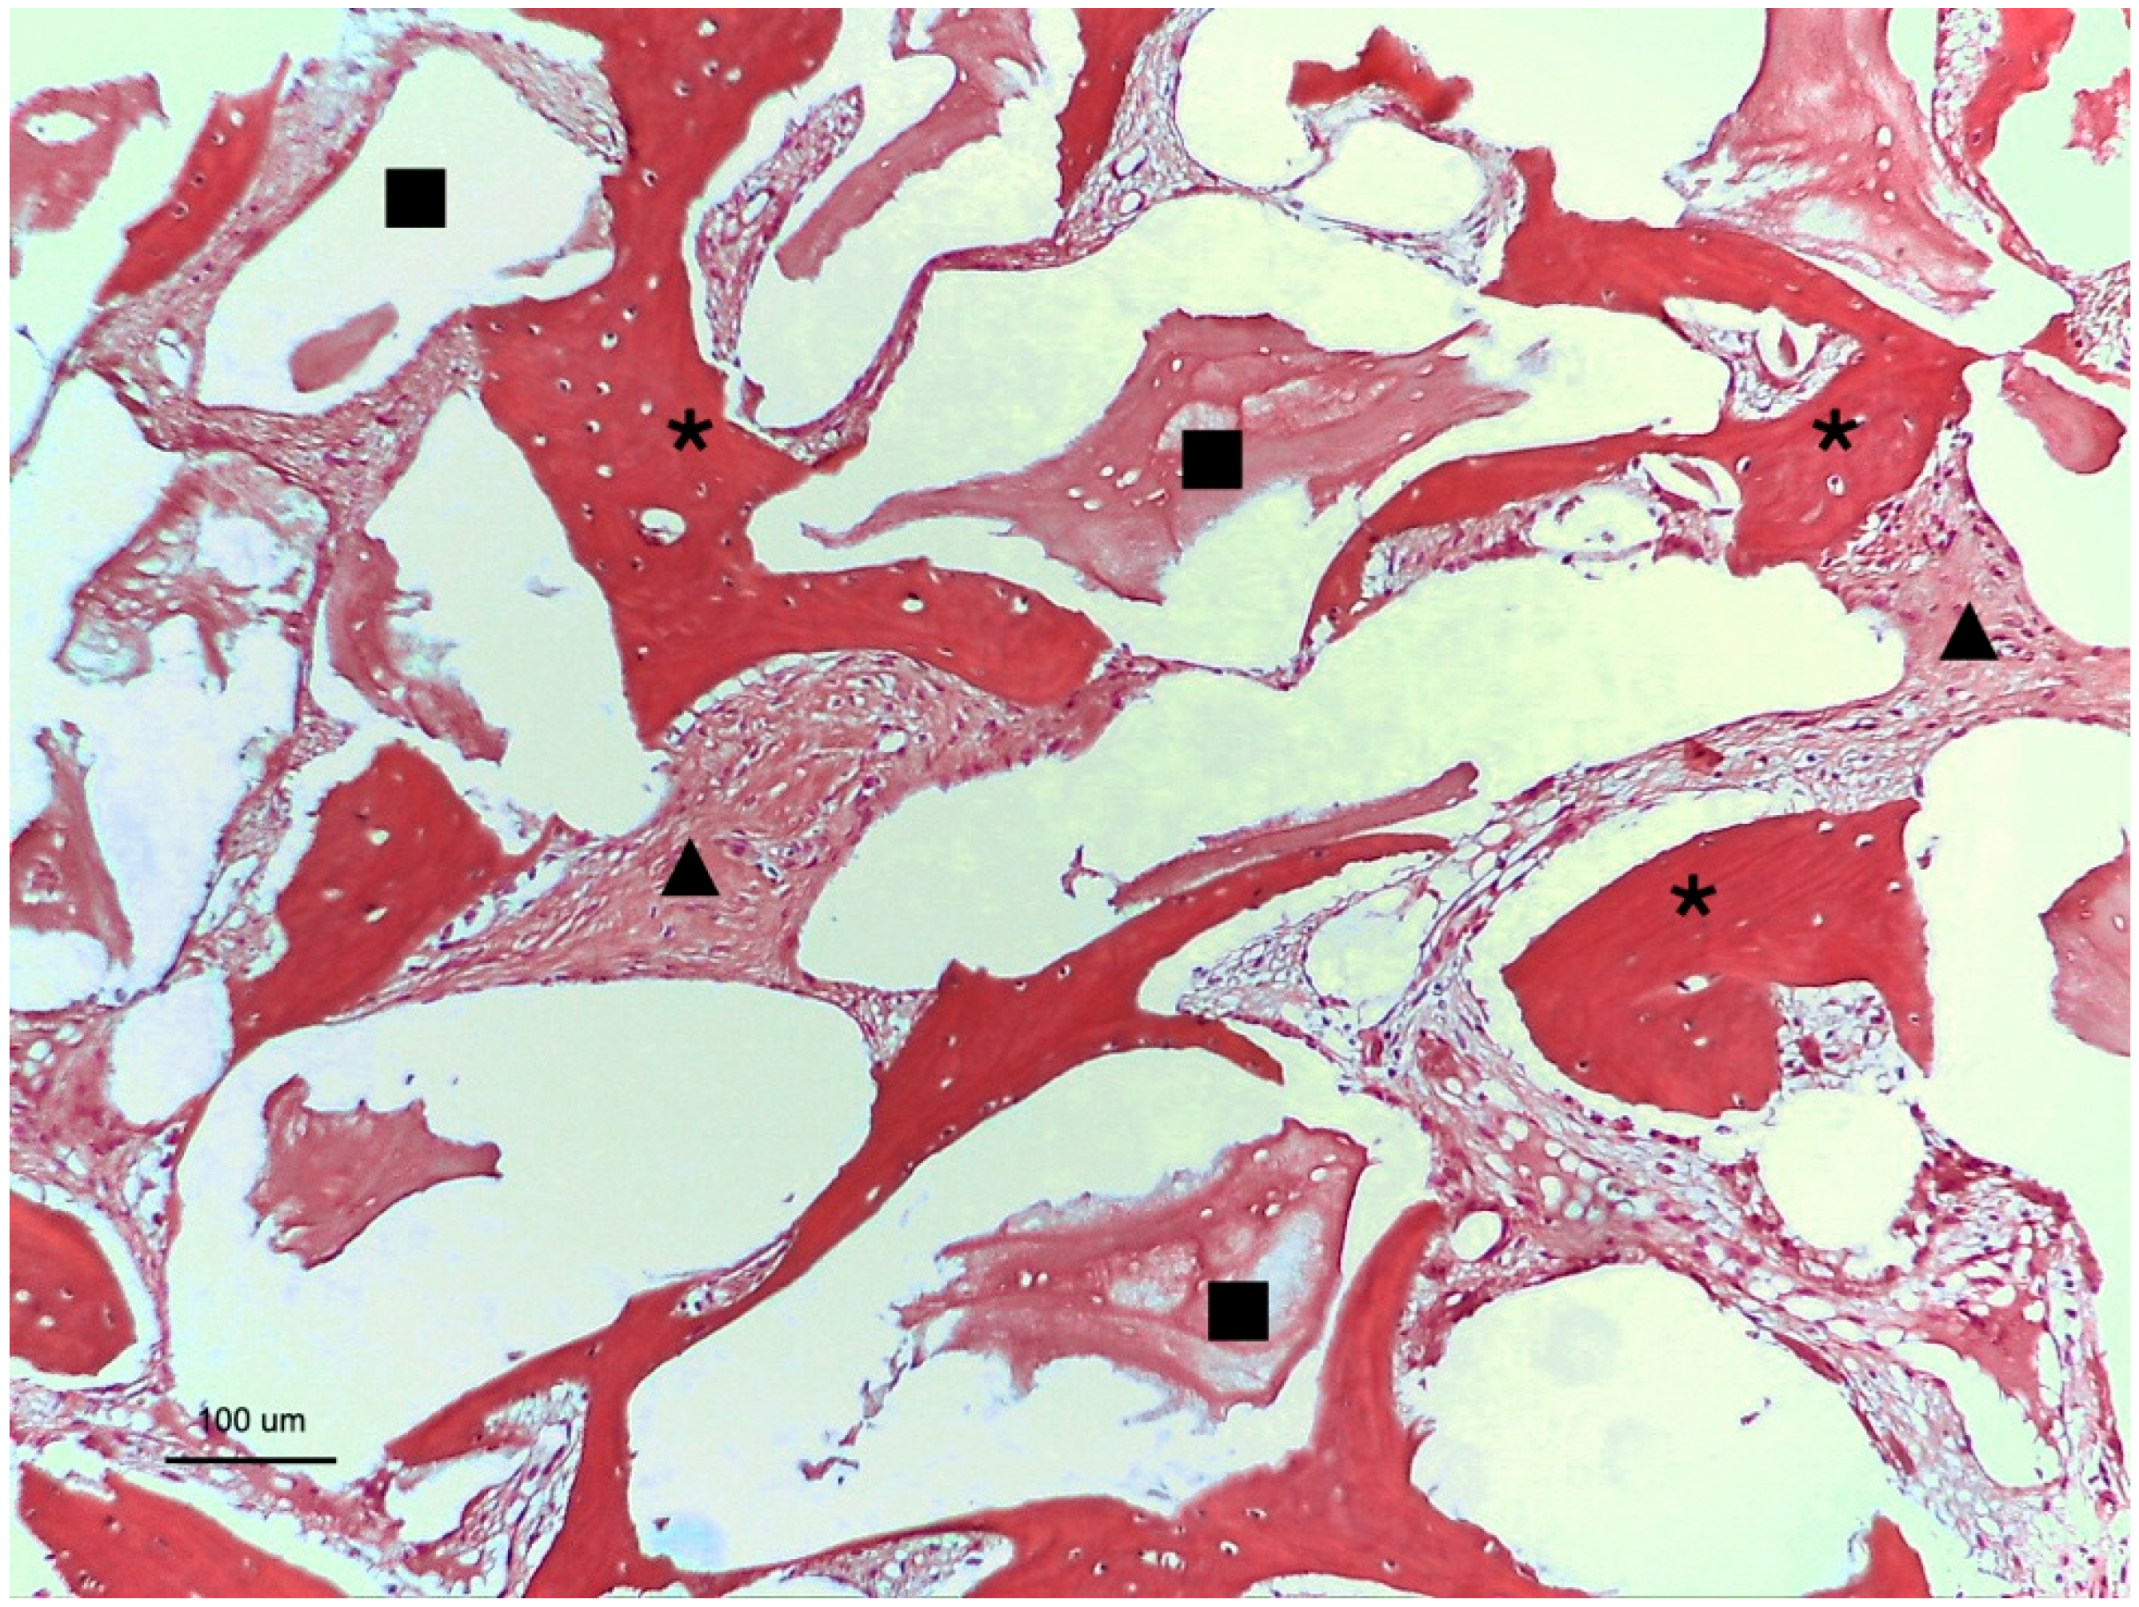

3.1. Group 1: Cerabone® Graft

3.2. Group 2: Bio-Oss® Graft

), and Cerabone particle (

).

), and Bio-Oss particles (

), Cerabone particle (

), and Bio-Oss particle (→).